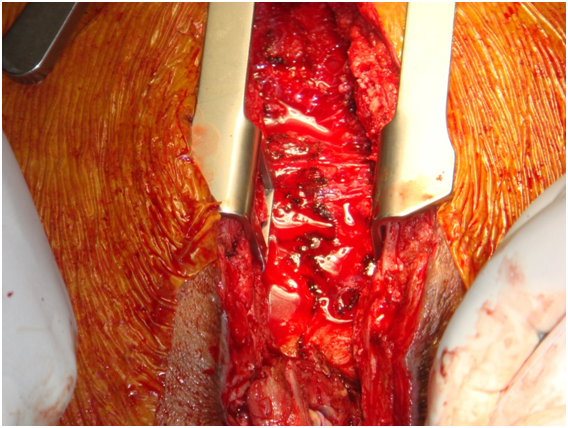

Chest incision was very technical-started from below with oscillator saw upto upper 1/3rd of sternum near aneurysm. Now upper part from above-near aneurysm curved the saw to right avoiding the aneurysm, put small retractor now gradually cut through bony surface so not went into graft and go around aneurysm without rupturing it but suddenly aneurysn came to leak--now no way--gentle pressure on leak and proceeded for total circulatory arrest. During going to total circulatory arrest, dissection around heart was done through diaphragmatic surface and right side. Now at 180C total circulatory arrest was done, taken out graft, found oval shaped opening at ascending aorta, a Dacron patch taken and covered it by continuous proline suture.

Started rewarming and circulation, Distal part of graft on axillary artery found-a silk ligature applied- rest of the graft taken out. Weaning from CPB was done easily, sternal wound reconstruction was done with pectoral is major muscle flap. The patient was discharge from the hospital on 7th post operative in good general condition. Now more than 2 years follow up he is doing very well [2] (Figures 1-10).

Figure 1: Aorto-axillary bypass-leak in aneurysmal aortic end.

Figure 5: Huge clot inside.

Figure 6: Under Total Circulatory Arrest proximal part of aorto axillary graft removed.

Figure 7: Oval shaped opening is found in aorta.